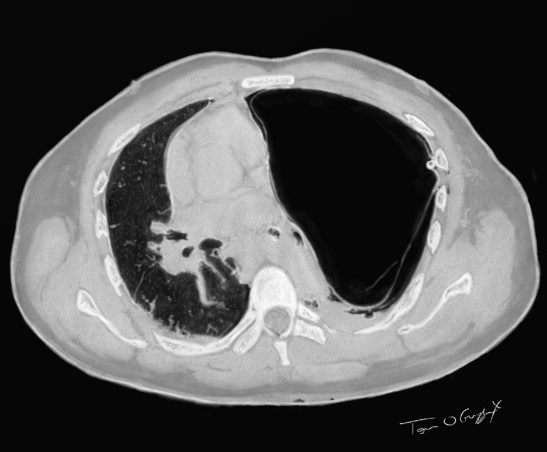

scanner bulle emphyseme drain thoracique